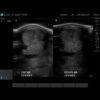

The U-Scan Ultrasound Standoff Pad was initially developed for use in equine ultrasound. However, it is possible to use in small animal ultrasounds as well. In addition, the linear probe can be used primarily for abdominal diagnosing, especially in cats for the small intestine and kidney – thus making the U-Scan an ideal standoff pad for enhancing ultrasound images.